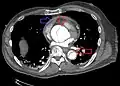

![]() | |

Stanford type B dissection of the descending part of the aorta (3), which starts from the left subclavian artery and extends to the abdominal aorta (4). The ascending aorta (1) and aortic arch (2) shown in the image are not involved in this condition. | |